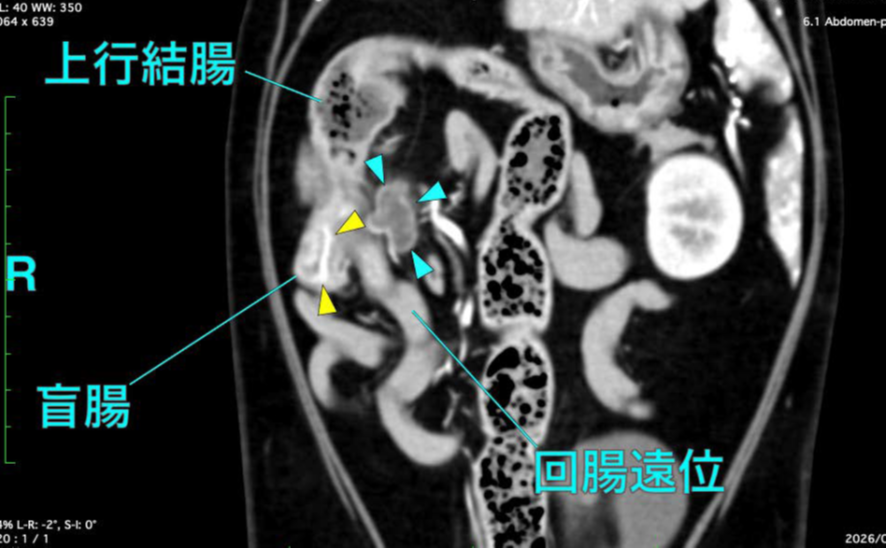

切除、脾臓腫瘍摘出(血管肉腫など)消化器外科、

胃切開/胃切除(異物摘出、胃捻転)、腸切開/腸切除吻合(異物、腫瘍、穿孔)、胆嚢摘出(胆嚢粘液嚢腫など)、肝葉切除(腫瘍、膿瘍)、会陰尿道造瘻(尿道閉塞)、卵巣子宮摘出(避妊、子宮蓄膿症)、精巣腫瘍摘出(去勢+腫瘍対応)、横隔膜ヘルニア整復、気管切開、